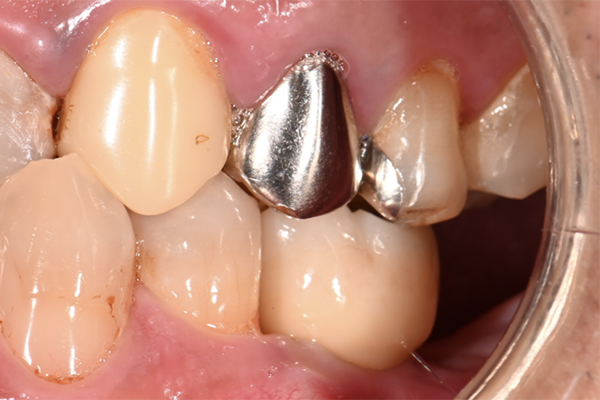

| 治療内容 | 左上奥歯のインプラント治療 |

| 治療期間 | 3ヶ月 |

| 治療費 | 87万円 |

| 治療 リスク | インプラントの土台を入れた後最終的な歯が装着されるまで仮歯をしていただきます |